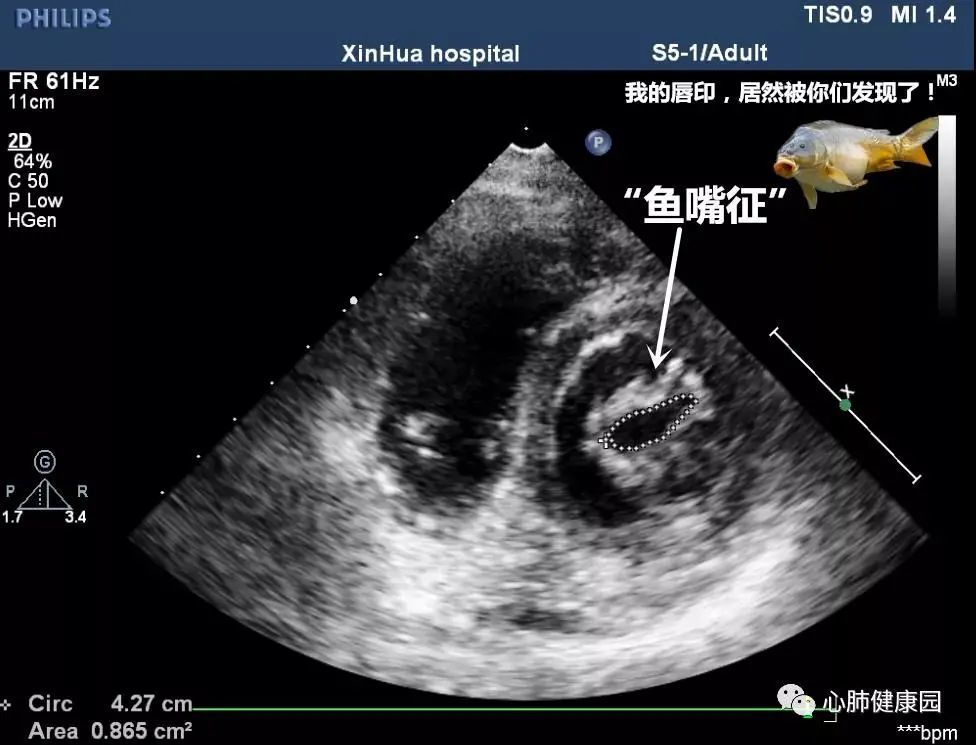

心瓣膜退行性病变----二尖瓣狭窄 - 超声医学讨论版 - 爱爱医医学论坛